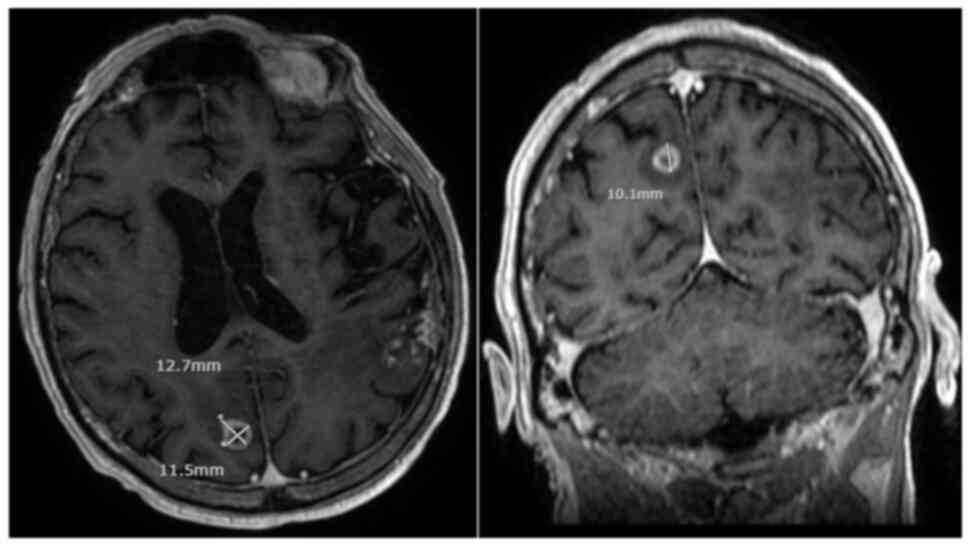

In late 2021, almost 6 years from his initial diagnosis, the patient began to experience episodes of transient aphasia. Repeat imaging of the head revealed a new enhancing mass in the right parietooccipital lobe measuring 1.1 cm in diameter, with no evidence of residual metastasis in the left hemisphere (Fig. 3). Further staging investigations did not identify any extracranial disease progression. Notably, the previous area of radionecrosis remained stable over time and the patient continued to deny any significant neurologic symptoms that would necessitate intervention. He went on to receive a second course of stereotactic radiotherapy, 30 Gy in 5 fractions, and will be monitored for treatment response. At the present time, the patient is functionally independent, ambulatory, and continues to participate within his local community by teaching firearm safety. His ECOG performance status remains unchanged. The timeline of the present case is shown in Fig. 4.

Figure 3.

Axial and coronal T1-weighted MRI of the head with contrast showing an ovoid enhancing mass in the subcortical white matter of the right parietooccipital lobe.